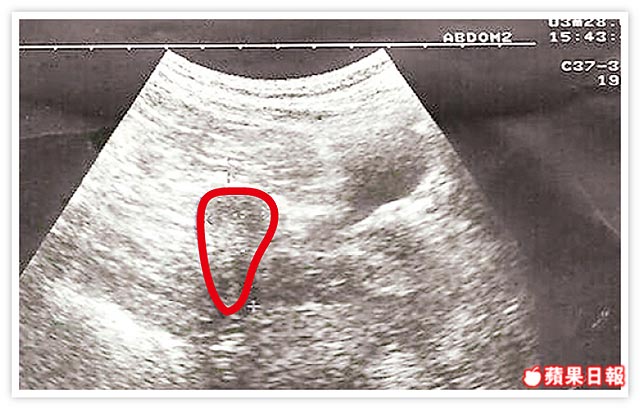

子宮鏡取胚胎 長庚創首例 婦產科醫師蔡鋒博表示,這名31歲婦人,經人工受孕懷雙胞胎,但妊娠第6周時,發現有一個胚胎不當著床於剖腹產傷口上,因此轉診       字級: ...